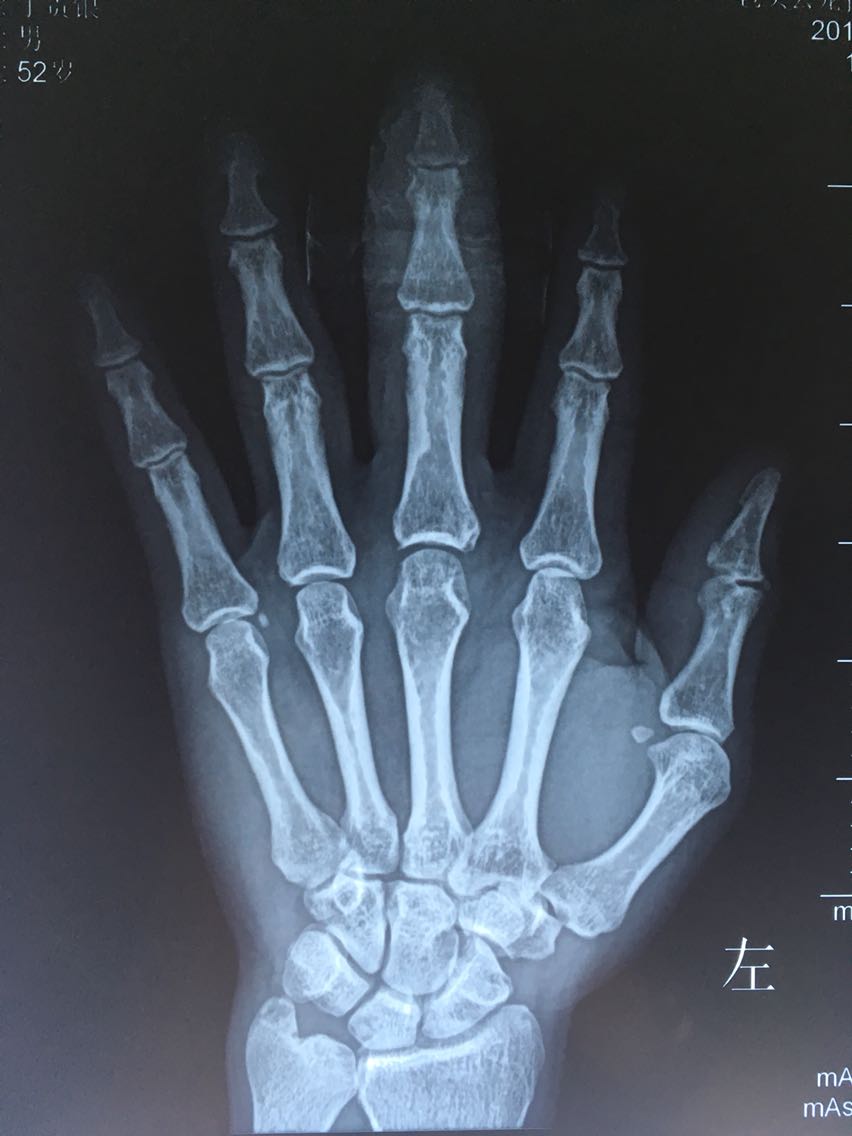

辅查:左手X光片可见骨质无明显异常,中指指体软组织影增粗,掌侧软组织影欠清晰。